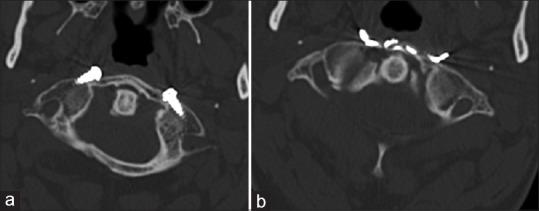

A transoral technique in which bilateral screws were placed intralaminarly and connected with wire was used to reduce and stabilize an anterior 1/2 fracture of C1.

Radiological studies after the surgery showed good cervical alignment, no screw or wire failure and good reduction with fusion of anterior arcus of C1.

Internal immobilization by this screw and wire osteosynthesis technique protects the mobility of the atlanto-occipital and atlantoaxial joints. The main advantage is that neither the twisted wires inserted under the anterior lamina, nor the laterally placed screw heads interfere with midline wound closure; unlike the plate/cage and rod systems used together with anterior screws. A computer navigation system with intraoperative 3D imaging facilities will be of benefit for safe placement of the screw, however we preferred a free-hand technique, as the starting point was at the fracture line along the trajectory of the routinely accessible anterior lamina.